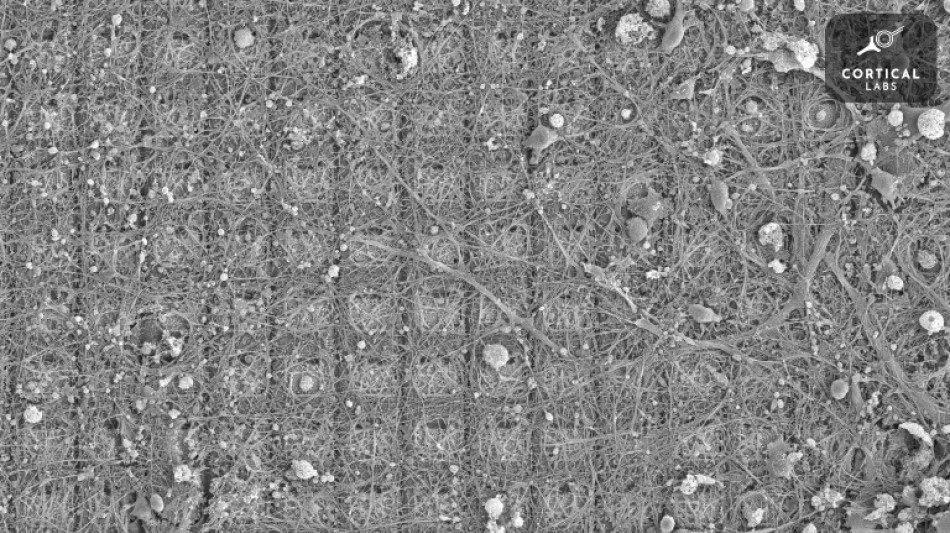

Des neurones doués de sensations ont appris à jouer à un jeu vidéo / Photo: Handout - AFP

Des neurones cultivés dans une boîte de Petri sont capables d'apprendre à jouer à Pong, le grand classique des jeux vidéo, faisant ainsi preuve d'un "comportement intelligent et doué de sensations", selon des chercheurs en neurosciences australiens.

Pour leur expérience, visant à découvrir s'il était possible d'exploiter l'intelligence inhérente des neurones, Brett Kagan et ses collègues ont prélevé des neurones de cerveaux embryonnaires de souris ainsi que des neurones issus de cellules souches d'humains adultes.

Ils ont ensuite cultivé ces neurones autour de matrices de microélectrodes capables de détecter leur activité et de les stimuler. Les expériences ont concerné des amas d'environ 800.000 neurones, la taille du cerveau d'un bourdon.